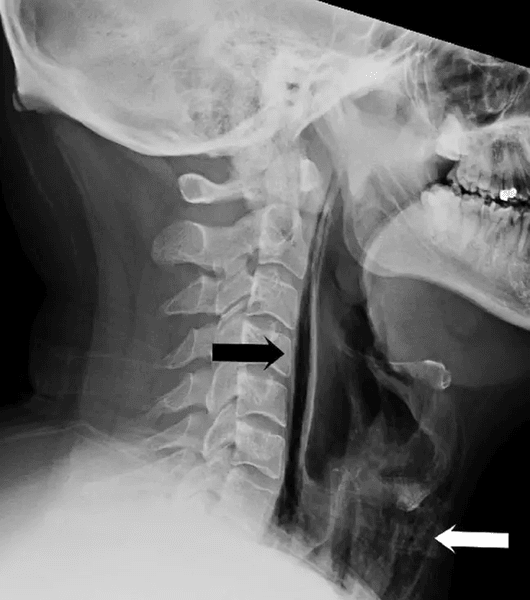

Врачи сказали, что струйки воздуха застряли в некоторых тканях горла и разорвали его. Спонтанный разрыв гортани встречается очень редко, обычно он вызывается рвотой, рвотным рефлексом, сильным кашлем или какой-либо травмой.

Спонтанный разрыв гортани встречается очень редко

Фото: BMJCaseReports